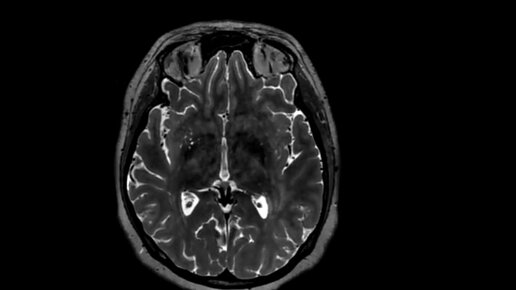

Как делают МРТ головного мозга, что видно (видео)